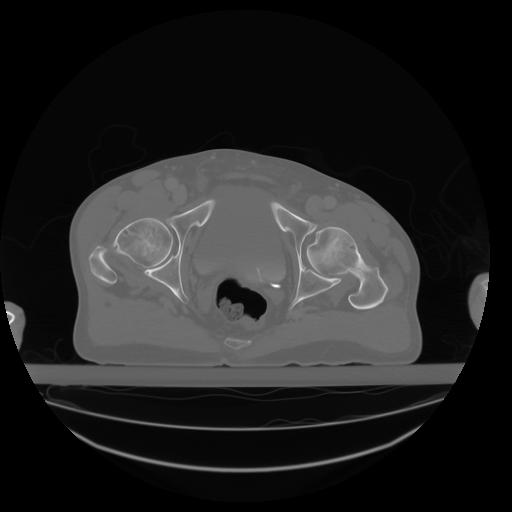

27 CUERPO,CE,Axial,3.0,CUERPO,,